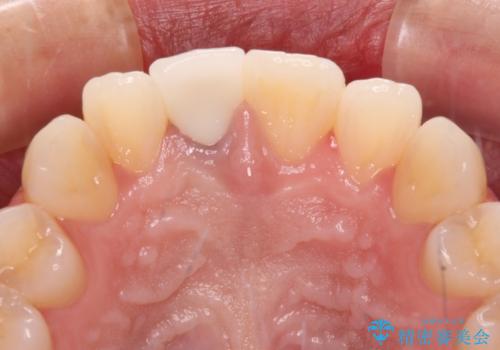

あっという間に気になっていた変色が解決し、早く治療を始めれば良かったとおっしゃっていました。

オーダーメイドタイプのクラウンを選択いただいたので、まるで天然の歯と見間違うほど自然に仕上がり、患者様には大変満足していただきました。